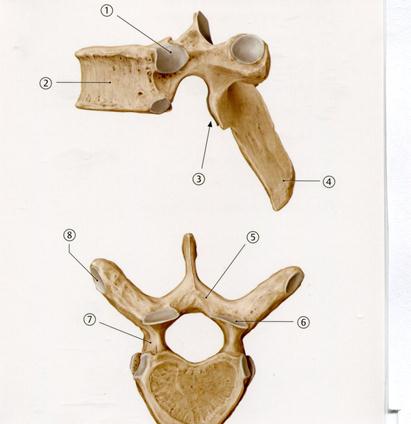

D. Бүйір массалар

++Е Көлденең өсінді

D. Жартылай сіңірлі

46. Төменде көрсетілген суреттегі белгіленген № 1 анатомиялық құрылымды атаңыз.

А. Доға аяқшалары

+С. Жоғарғы буын беті

D. Қабырғалық шұңқырша